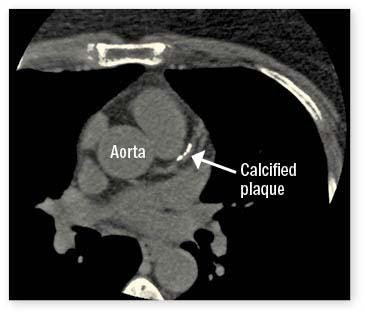

Liz, an artist living in North Carolina, had a CT scan several years ago to evaluate a torn muscle in her upper abdomen. The radiologist’s report included some additional concerning information: “Coronary arterial calcification much greater than expected for patient’s age.” Calcification is a marker for heart disease, since the fat-laden plaque that accumulates inside arteries often contains calcium, which is visible on CT scans. Liz, who was 56 at the time, consulted a cardiologist about the discovery. Four years later, she had bypass surgery to treat two severely narrowed coronary arteries.